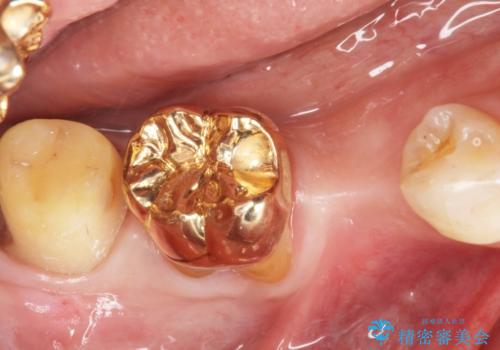

親知らずを抜歯して隣の歯のう蝕を除去し、歯肉の治癒をしっかり待ったのち、患者様のご希望によりゴールド(PGA)クラウンによる補綴を行いました。

右下7:ゴールド(PGA)クラウン